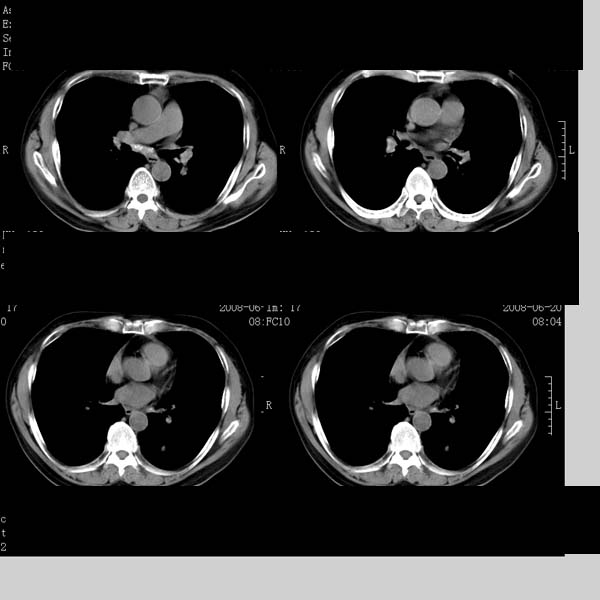

以下是引用守望可可西里在2008-6-24 1:11:00的发言:[br][br] 考虑为周围型肺癌:[br] 1.分叶结节,形态极不规则,蟹足样伸展的恶性浸润特征比较明确。[br] 2.磨玻璃影中由多个更高密度小结节聚集呈梅花瓣样。[br] 3.局部胸膜凹陷征比较明确。[br][br] 另:纵隔胸膜明显增厚、粘连。

以下是引用zjzjr在2008-6-24 11:19:00的发言:[br]支持左下肺周围型肺癌伴右肺转移,纵隔淋巴结转移,心包积液.

以下是引用zhangling在2008-6-24 14:56:00的发言:[br]我们科室意见报告为[br][br]1考虑左下肺周围型肺癌[br]2右肺小结节考虑转移瘤,纵隔淋巴结转移[br]3心包积液. [br] 各位老师分析的相当好 谢意[br]